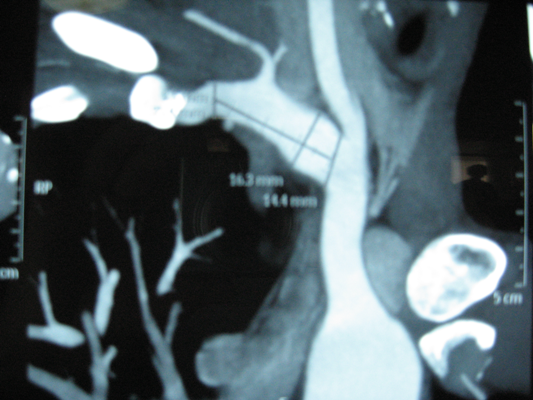

Cận lâm sàng: Echo, AngioScan (hình dưới).

Chẩn đoán: Phình đoạn đầu động mạch dưới đòn phải.

Hình 1: Chụp AngioScan cho thấy khối phình ngay nơi xuất phát từ TABC, kéo dài qua động mạch đốt sống